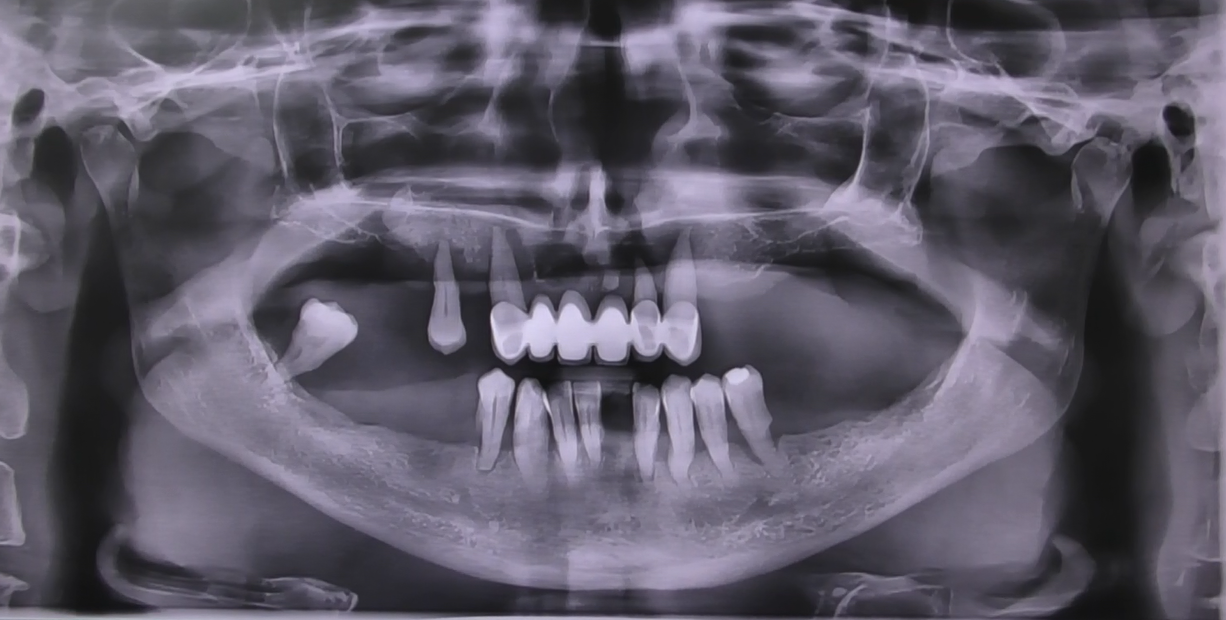

Il nostro team valuta attentamente le condizioni del paziente, registrando le zone con riassorbimenti anomali, atrofie e quelle dell’osso non longilineo. In un’interfaccia diretta tra implantologo e protesista, affrontiamo ogni aspetto negativo, creando un piano personalizzato per il ripristino della masticazione.

Ulteriore caso clinico